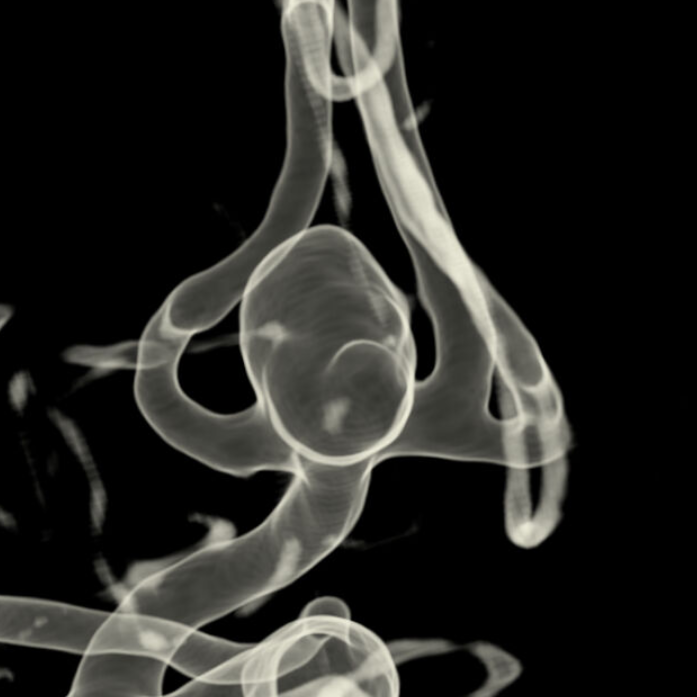

Tutkijat tarkastelivat aivovaltimopullistumien eli aneurysmien hoidon laatua. Tutkimuksessa seurattiin 169:ää potilasta, joita hoidettiin HUSissa joko mikrokirurgisesti (29 prosenttia potilaista) tai suonensisäisesti (71 prosenttia) joulukuun 2022 ja elokuun 2024 välisenä aikana.

miikka.korja@hus.fiKuvat